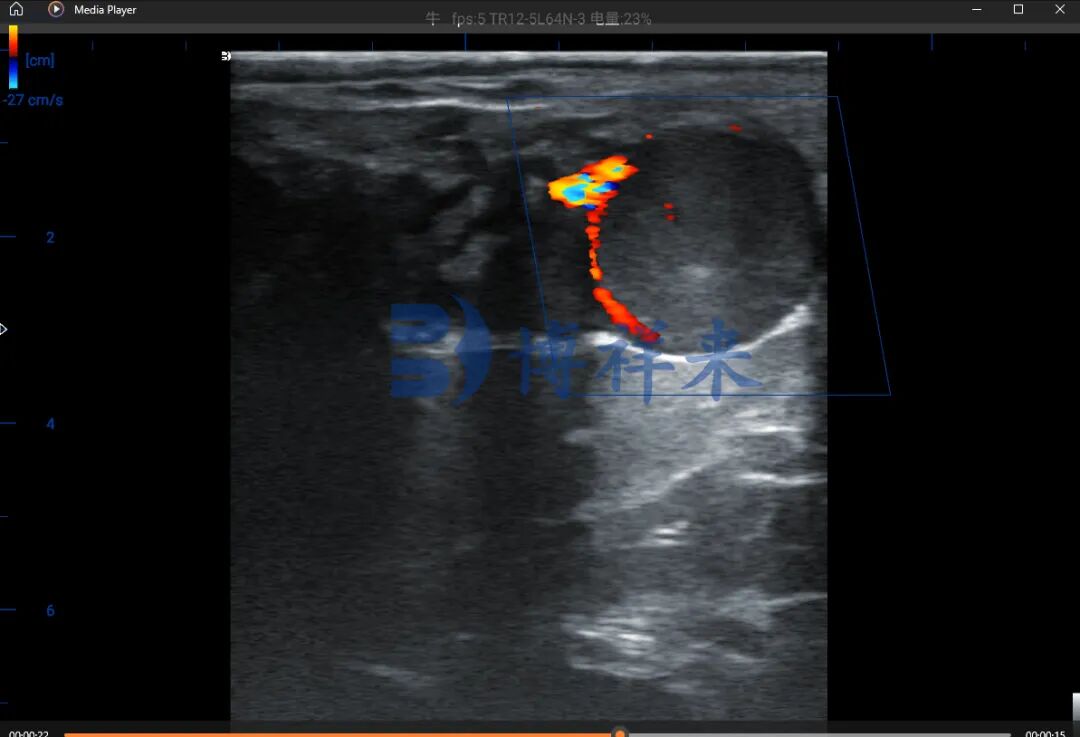

在卵巢检查中,卵泡常表现为边界清晰、内部为黑色液性暗区的圆形结构;而黄体则表现为灰白色实性回声,有时带有小腔隙。功能性黄体在彩色多普勒下可见丰富血流,而退化性黄体血流稀少,根据这个特性使用多普勒彩超检测黄体血流情况可以在 21天 确定母牛妊娠情况

多普勒B超机测牛21天妊娠

牛黄体血流影像图(21天怀孕)